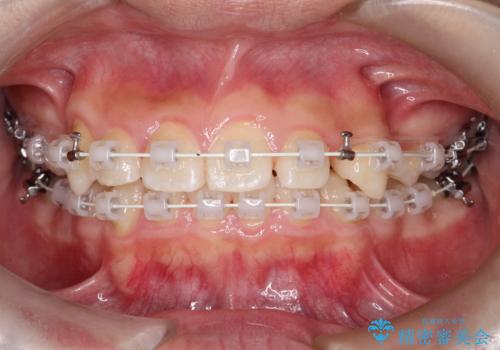

八重歯・歯並びのデコボコとディープバイトを改善した抜歯ワイヤー矯正症例

- ワイヤー(審美装置)

矯正の精密検査の結果上顎左右4番の計2本を抜歯し、審美性に配慮したワイヤー矯正装置(審美装置)を用いて治療を行いました。

八重歯などの歯列のデコボコが綺麗に改善され、患者様にも大変喜んでいただけました。また、咬み合わせが深い「ディープバイト」も併せて改善し、見た目だけでなく機能面でもバランスの取れた咬合を獲得しています。